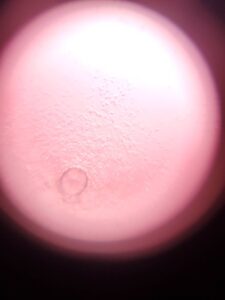

成功率1%への挑戦

petitIBIS-D6-1.